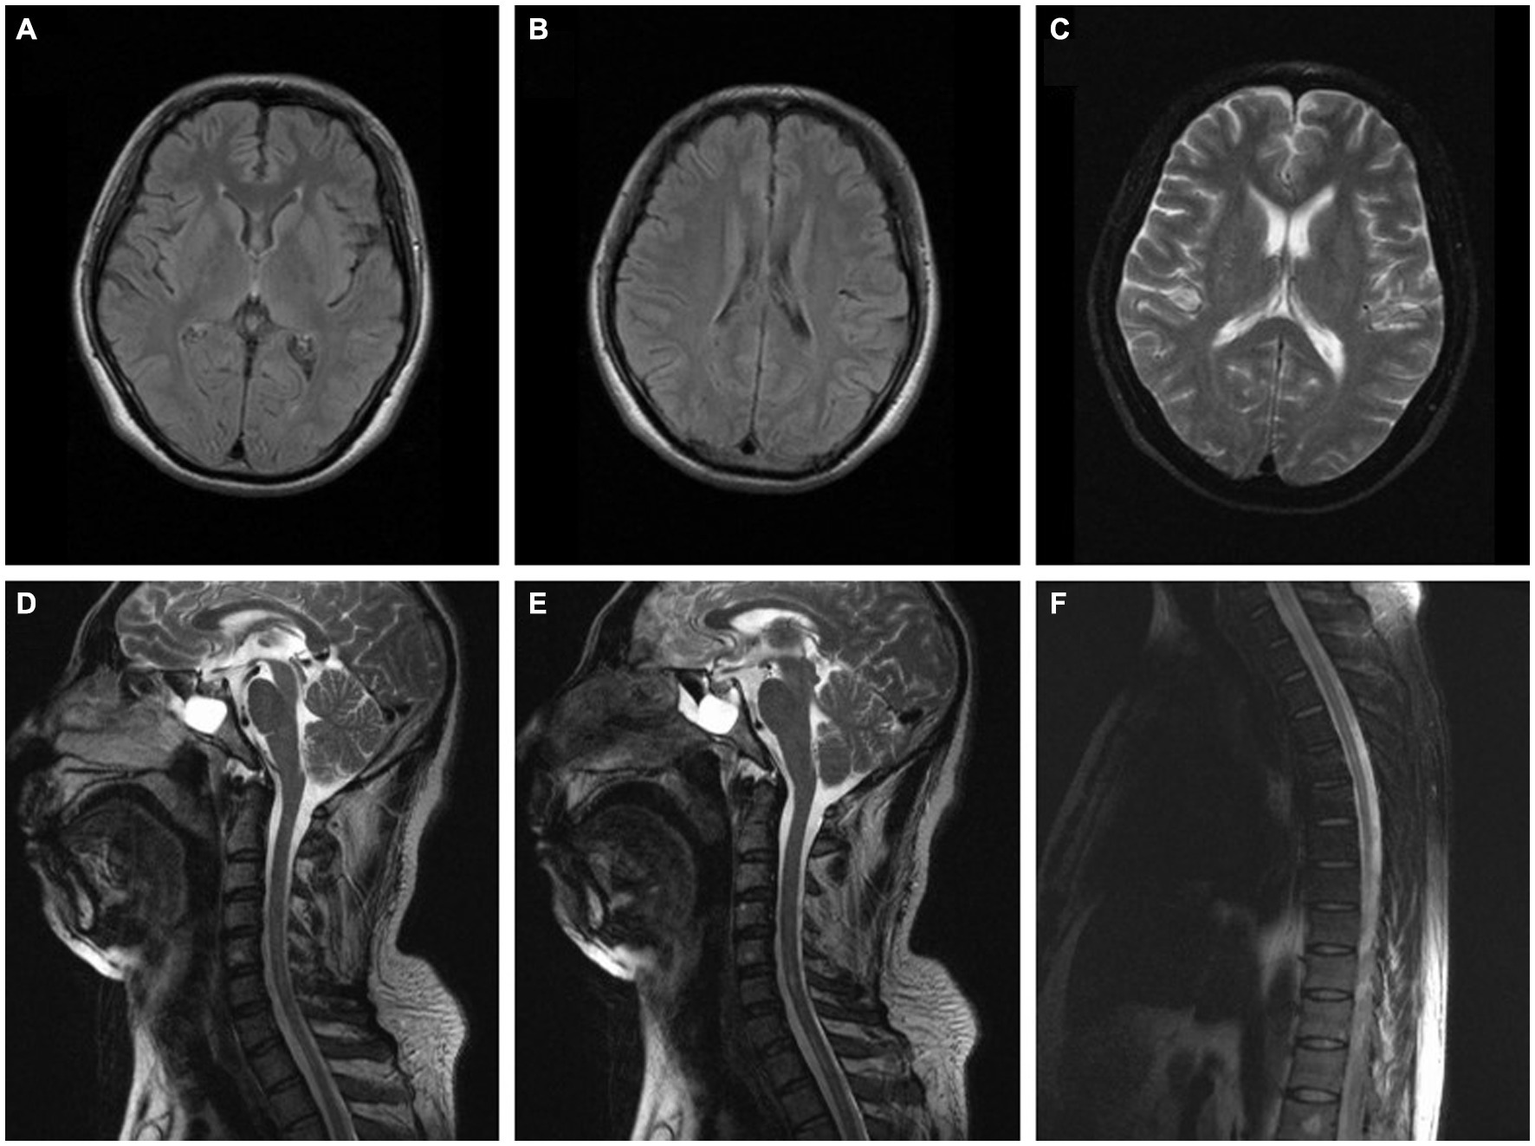

Figure 2

(A–C) Brain MRI of the patient in case 2 was normal (2 months after onset). (D–F) Spinal MRI of the patient in case 2 indicated longitudinal linear abnormity with long T2 signal in the cervical and thoracic spinal cord and was not enhanced on the contrast-enhanced scan (2 months after onset).